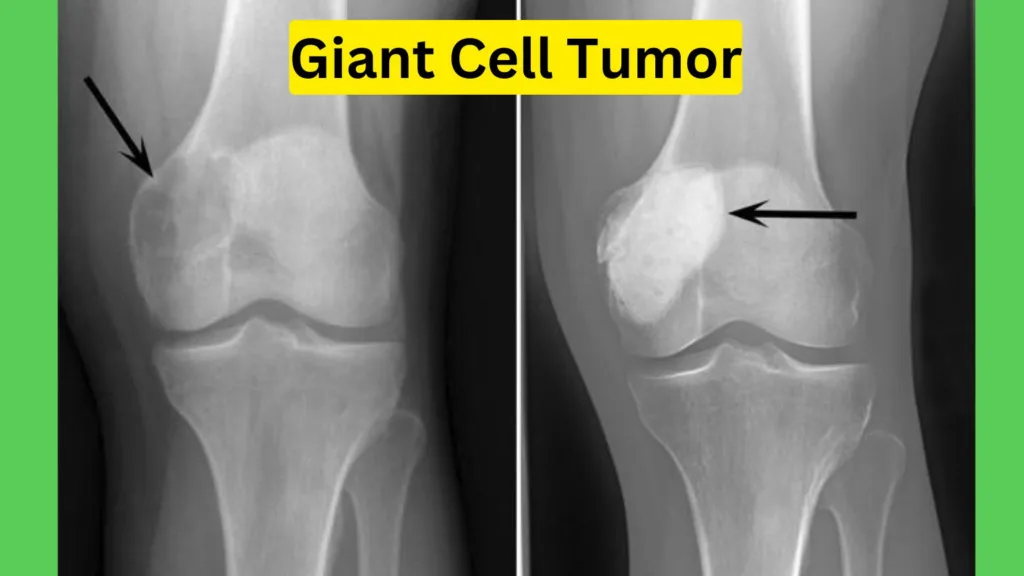

Giant Cell Tumors are bone tumors characterized by the presence of multinucleated giant cells. These tumors typically occur in the epiphysis of long bones, such as the distal femur, proximal tibia, and distal radius.

Ans. Giant cell tumors are relatively uncommon, accounting for only about 5% of all primary bone tumors. They primarily affect young adults between the ages of 20 and 40, with a slight predilection for females. While they can occur in any bone, they most commonly develop in the long bones near the knee joint, such as the distal femur or proximal tibia.